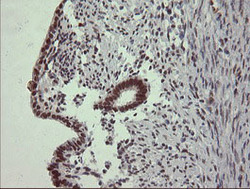

Supportive validation

- Submitted by

- OriGene (provider)

- Main image

- Experimental details

- Immunohistochemical staining of paraffin-embedded Human endometrium tissue within the normal limits using anti-TRIM22 mouse monoclonal antibody. (Heat-induced epitope retrieval by 10mM citric buffer, pH6.0, 120C for 3min, TA505281)

- Validation comment

- IHC